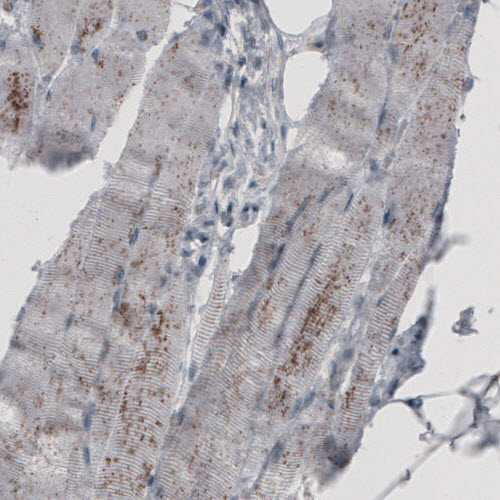

Immunohistochemical staining of human kidney shows granular cytoplasmic immunoreactivity in renal tubules.